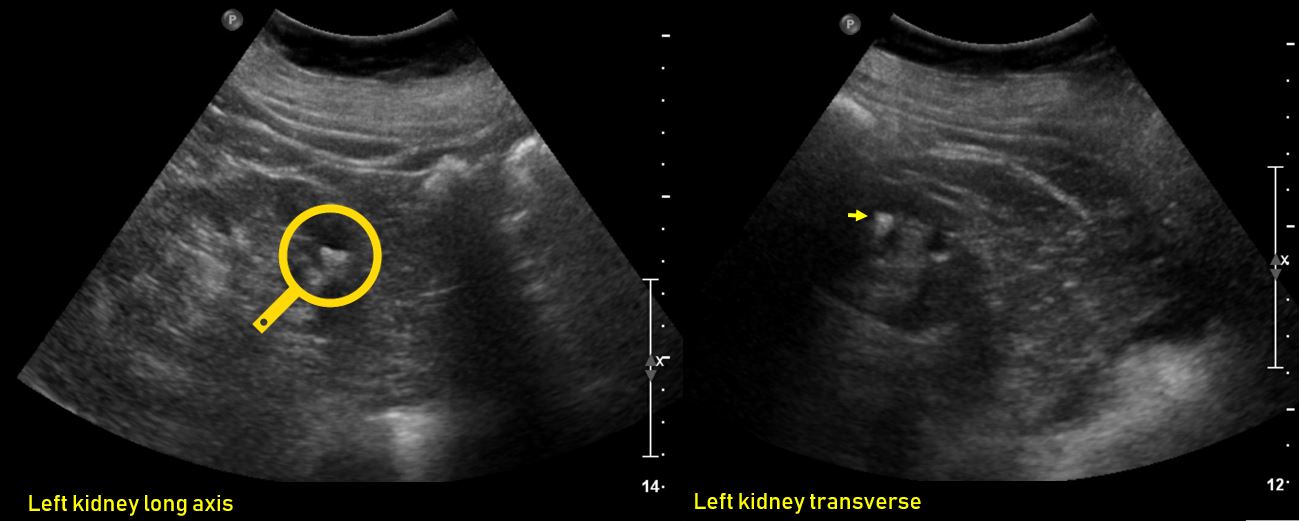

From www.renalfellow.org

Ultrasound features of Kidney Cysts Renal Fellow Network What Causes Calcium Deposits In Kidneys nephrocalcinosis is a condition in which calcium levels in the kidneys are increased, leading to generalized deposition of. calcium deposits in the kidney cause a condition known as nephrocalcinosis. the clinical presentation and prognosis of nephrocalcinosis. People with this may also have high levels of calcium or. problems with the kidney or the parathyroid (four small. What Causes Calcium Deposits In Kidneys.